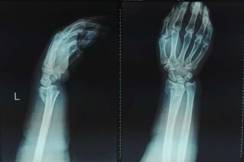

手法复位小夹板固定治疗骨折

中医特色优势技术包括手法、中药及特色器具综合治疗颈椎病、腰间盘突出症、腰椎退变性疾病的阶梯治疗、股骨头坏死的系列治疗、膝关节骨性关节炎的阶梯治疗;手法复位小夹板治疗儿童肱骨髁上骨折、尺桡骨骨折、桡骨远端骨折等及各部位关节脱位。中药制剂“生肌膏”被录入非物质文化遗产。自主研制的骨伤科中药制剂如脊椎病方、腰椎间盘突出症方、骨性关节炎方、滑膜炎方、骨质疏松症方、骨折早中后期方、股骨头坏死方、金黄膏散、活血膏、活血消肿膏、接骨甲乙丹等拥有很高的社会认可度。

中医外治疗法是我科另外一项突出特色,我科开展中医正骨整脊门诊,对于急性斜颈;寰枢关节错位;钩椎关节紊乱症;急性颈椎间盘突出症;颈椎椎曲异常综合征(颈椎失稳症);颈椎管狭窄症;颈腰椎间盘病;胸背肌筋膜炎;腰椎后关节错缝症;颈脊源性血压异常症;青少年特发性脊柱侧弯症临床疗效优良。闭合复位小夹板外固定方法尽显中医优势:既起固定作用,又对伤肢软组织无损伤,保持正常血运,不影响骨折正常愈合;防止伤肢再移位,能避免不利于伤肢愈合的有害应力;对伤肢各关节约束少,为早期功能锻炼创造条件;对骨折整复后的残留移位,通过压垫和小夹板固定,肌肉舒缩,可有矫正作用,完美遵循中医骨伤治疗理论。外敷外治尽显中医风采。我科采金黄膏、金黄散(外用)治疗膝关节滑膜炎,无名肢体肿痛,肩肘腕踝关节肿痛疗效显著。生肌散生肌膏辩证外敷治疗创面不愈合及创面感染疗效显著。接骨甲丹,接骨乙丹辨证贴敷促进骨折愈合。活血膏,活血消肿膏用于肢体肿痛,关节肿痛疗效甚佳。

西医手术先进全面:运用DCO理念,阶梯序贯抢救及治疗严重骨盆骨折、多发性、开放性重大骨折创伤;常规开展复杂骨盆髋臼骨折、手足显微外科的手术治疗;以最先进的生物学固定理念为指导,运用微创手术技术治疗骨折,包括:四肢长骨骨折的交锁髓内固定技术、MIPPO(微创经皮钢板内固定技术)、股骨近端骨折髓内固定技术(PFNA)、外固定支架固定技术等等均达国内先进水平。

中医骨伤特色明显:包括特色复位手法、传统夹板传承并革新;中药经验方药内服、外敷及离子导入疗法、中药水浴、熏蒸以及骨折后康复治疗等等可有效促进骨折愈合、治疗骨不连;吊兜悬吊牵引结合功能锻炼保守胸腰椎压缩性骨折;骨髓炎广泛开窗换药+外固定支架技术、感染骨段切除骨延长技术治疗,结合中医药辩证治疗等。